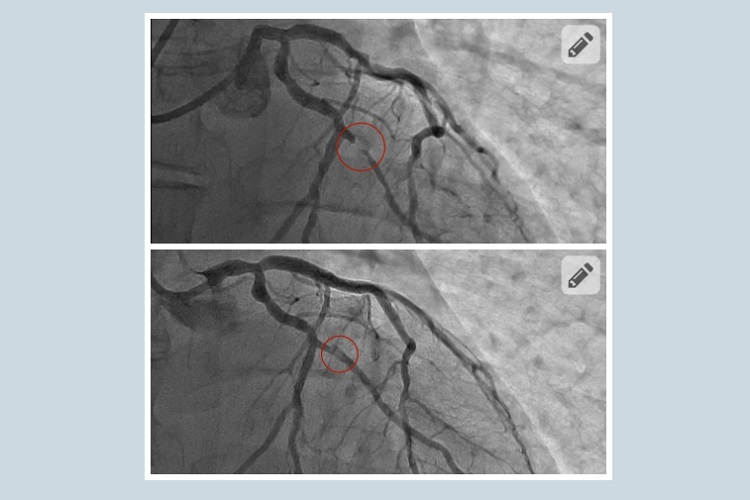

«Це був передінфарктний стан. Це вже критичний момент, коли така сильна задишка у пацієнта з’являється навіть у стані спокою. Ми одразу провели коронарографію і виявили багатосудинне ураження коронарних артерій», – каже Василь Процько, завідувач відділення кардіології та інвазивної терапії лікарні святого Пантелеймона.

Під час виконання цієї малоінвазивної внутрішньосудинної операції лікарі загалом виявили чотири субоклюзії, себто критичні звуження. Дві судини спеціалісти розширили стентами, які завели через сантиметровий розріз на руці. Ще дві з меншим звуженням – роздули балонами. І таким чином повністю відновили нормальне кровопостачання серця. Як все відбувалося пацієнт бачив на власні очі, адже всю операцію був при свідомості.